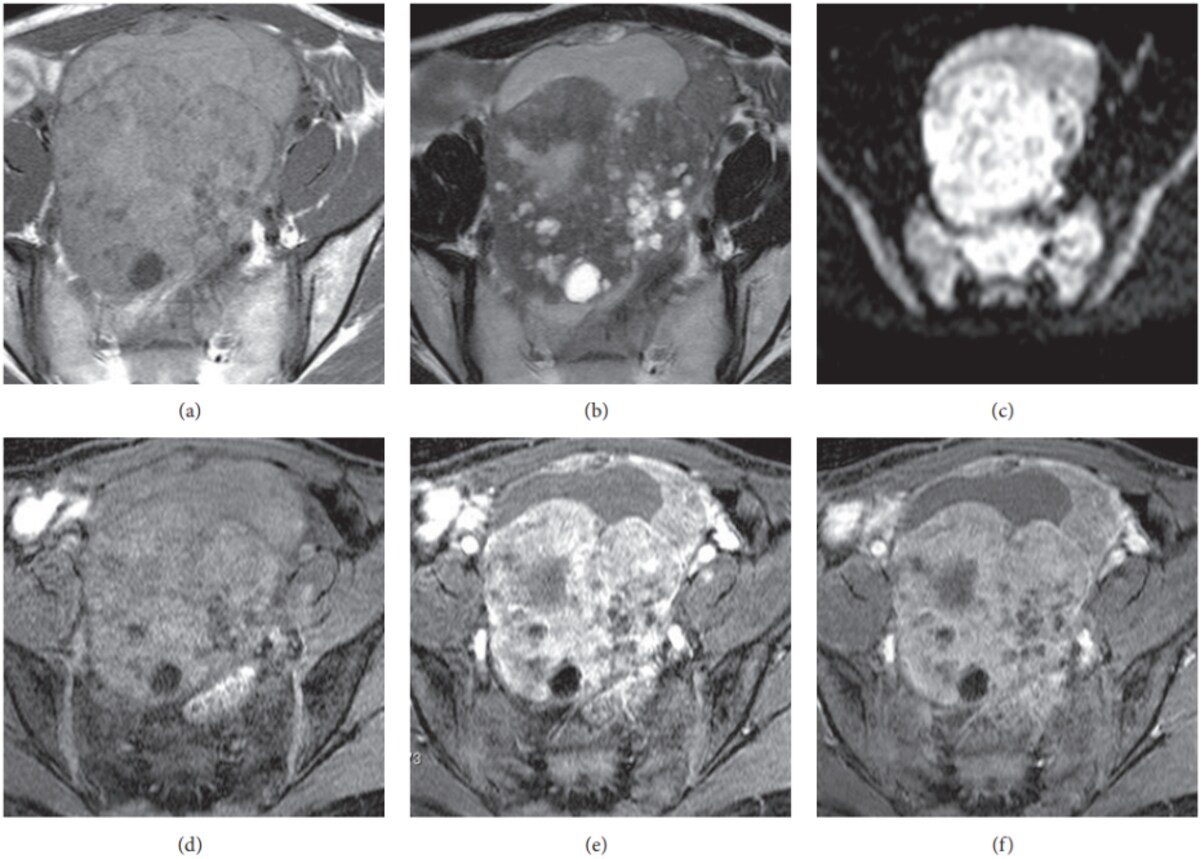

MRI clearly distinguishes fluid from solid tissue, showing whether a mass is mainly cystic, mainly solid, or mixed, and whether there are papillary projections, thick septa, or necrosis that raise concern for malignancy. Dynamic contrast and diffusion-weighted sequences further separate benign-appearing cysts from more suspicious, highly vascular, or diffusion-restricted solid components25.

T2-weighted images make fluid appear bright and dense fibrous tissue appear darker, which helps show the overall shape and internal structure of an ovarian mass35. Radiologists use T2 to assess how many cystic spaces there are, how thick the walls and septa are, and whether there are internal solid nodules or papillary projections.

DWI assesses how water molecules move within tissues. Tumours tend to restrict water movement, so they stand out as areas of restricted diffusion36–38. This helps in identifying and confirming suspicious lesions, even when they are small or subtle.

This is a map derived from DWI that provides a numerical value to help separate aggressive cancers (which have lower ADC values) from less aggressive tumours. Lower ADC suggests increased tumour cell density36,37.

DCE captures images over time after a contrast dye is injected. Malignant tumours often soak up the dye earlier than normal bladder wall tissue, a sign of abnormal blood vessels36,37,39. This helps distinguish cancer from benign tissue and is useful for staging and treatment monitoring.